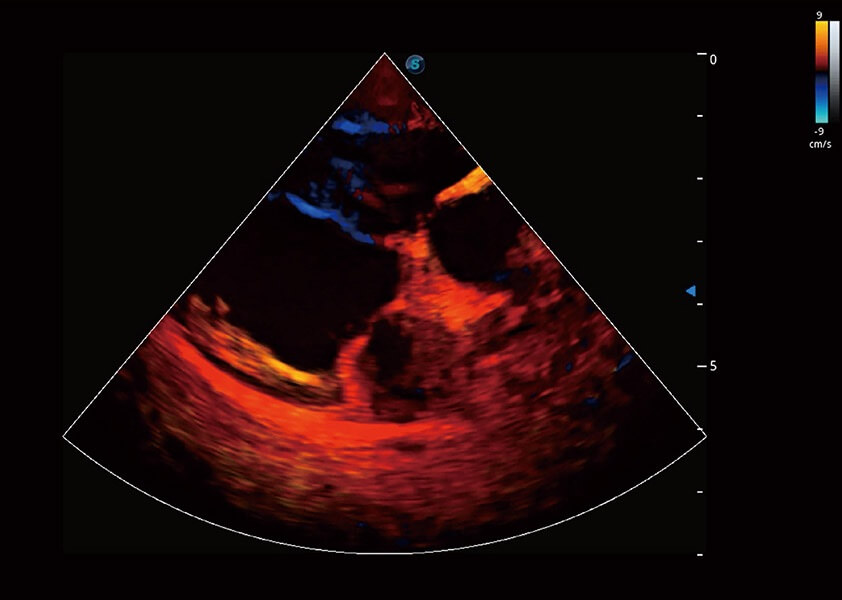

ProPet 60 作为一款高端台式动物超声设备,为动物医生的日常诊断提供了一系列贴合动物临床需求、解决临床实际问题的高级成像功能。凭借全系列高清探头,满足医生对腹部、心脏、生殖、浅表、肌骨等成像的所有需求,切实帮助您提升检查效率,提高诊断信心。

兽用彩色多普勒超声诊断系统

动物是人类最亲密的朋友和最值得信赖的伙伴。16877太阳集团也一直致力于探索动物专用的超声影像解决方案。 全新推出的ProPet系列,是16877太阳集团在动物超声影像智能化、专业化、精准化的一次跨越式革新。动物不能用言语来表述自己的不适,通过超声影像,ProPet系列搭建了动物医生与不同物种沟通的“桥梁”,为动物医生注入了“治愈之力”。